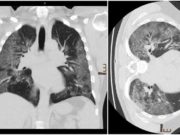

Cum arată radiografia la plămâni a unui medic infectat cu Covid-19

Medic infectat cu Covid-19Radiografia arată răspândirea virusului